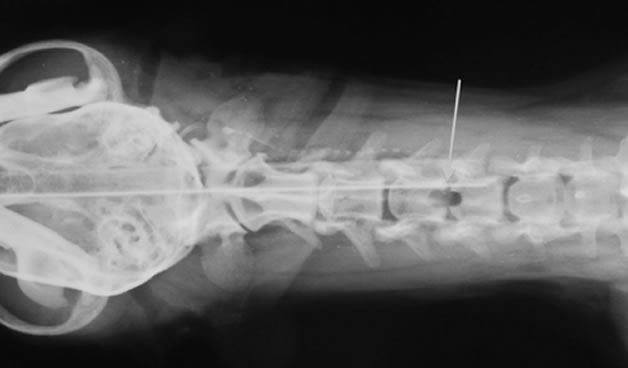

脊椎骨折、脱臼

症状:腰背部の痛み、前肢と後肢もしくは後肢の歩様失調や麻痺

頸椎、胸椎、腰椎、仙椎の骨折や脱臼。多くは交通事故や高所からの落下などの外傷にともなって起こります。診断にはレントゲン検査、脊髄造影検査、CT検査、MRI検査などが必要です。骨折や脱臼が生じた部位や重症度によって手術方法は変わります。